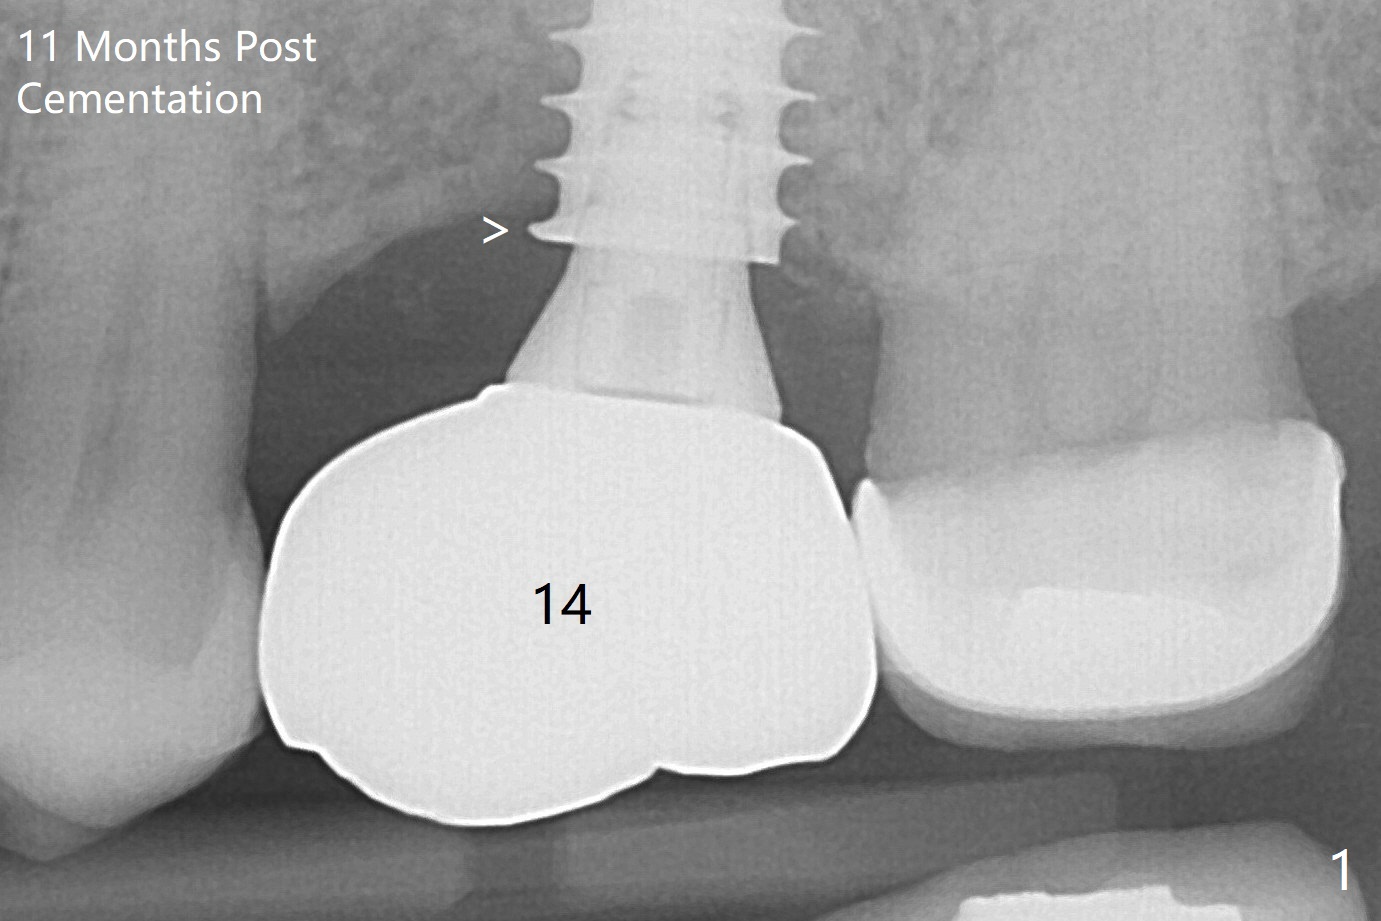

A 57-year-old woman complains of bad smell while use of water flosser between 11 and 21 months post cementation of implant crown at #14 (Fig.1,2). Bone loss is more obvious with CBCT (Fig.3,4), in spite of apparently normal gingiva around the implant after removal of the abutment and crown (Fig.5). In fact the buccal (B) gingiva is fragile with easy access to the underlying implant plateau. Following flap elevation, the bone loss is evident (Fig.6), but the implant plateau is slightly subcrestal (Fig.7 *). The exposed implant threads are covered with the 1st round of bone graft (Fig.8). After 2nd round of allograft (Fig.10-12) and collagen membrane, the flaps are approximated (Fig.9). The wound is covered by acrylic dressing. The latter is loose, but stays in place 1 week postop (Fig.13). Due to short neighboring teeth, the acrylic dressing is able to be removed with wiggling; it appears that the wound is healing (Fig.14). The dressing returns for another 2 weeks; some of the graft has been lost (Fig.15). The dressing does not return 7 weeks postop, since the wound is healing (Fig.16).